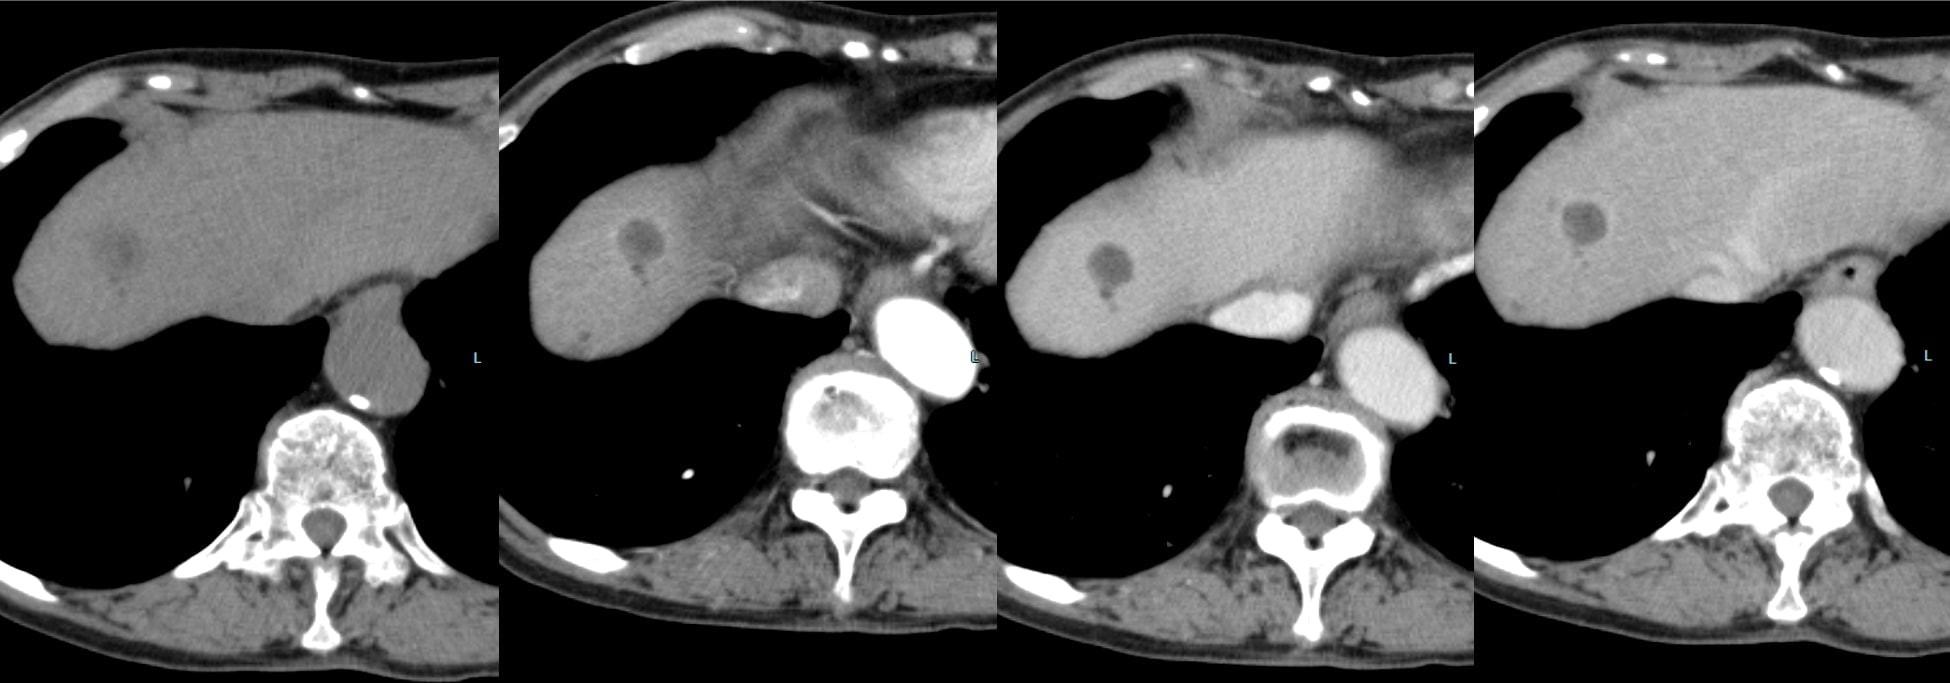

60歳代、女性、53kg、HCC

C型肝炎でフォロー中に肝腫瘍の指摘あり。前医CTにて肝内胆管癌が疑われ、手術目的に当院紹介。肝腫瘍の術前精査目的に再度造影CTとEOB-MRIを施行した。

Necrotic HCCと診断され、切除術を施行された。病理診断でも No residual carcinoma with necrosisとの診断であった。その後再発を認めず、経過観察となっている。

本症例におけるEOB・プリモビスト造影MRIの役割について